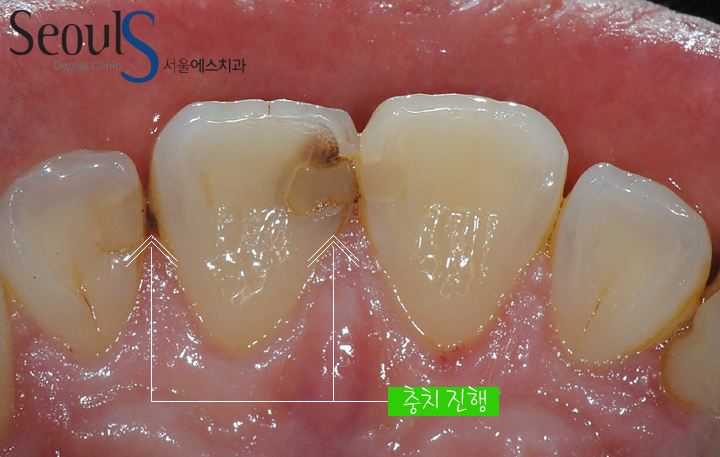

20160915-leetea-1정면 치아모습입니다

앞니에 충치가 진행되고 있습니다

충치 때문에 치아 표면이 검게 변색 되었고 치아 사이에 진행되고 있는 충치가 보입니다